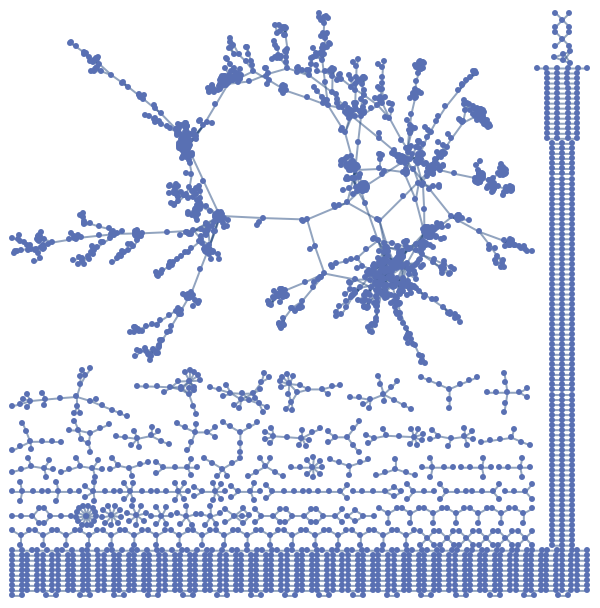

A bipartite network of diseasome linked by known disorder-gene associations

A network of disorders and genes linked by known disorder-gene associations, indicating the common genetic origin of many diseases. Genes associated with similar disorders show both higher likelihood of physical interactions between their products and higher expression profiling similarity, supporting the existence of distinct disease-specific functional modules. Annotation values contain "Type" and "ID".

(3061 vertices, 2673 edges)